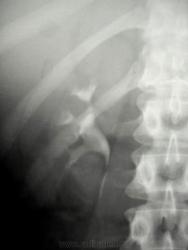

Вы считаете, что представленное демонстрирует псоас - симптом?

"Краевой псоас-симптом (Rand psoas-symptom). При этом симптоме тень лоханки по наполнении ее контрастной жидкостью оказывается резко ограниченной с медиальной стороны латеральным краем поясничной мышцы. Это ограничение имеет строго прямую линию, идущую параллельно m. psoas, слегка в косом направлении" - источник http://www.uroweb.ru/catalog/med_lib/rg_ur/ren20.htm Если не так - поправьте, пожалуйста.

В выставленном случае "левосторонняя почечная колика-3" Людмилы Григорьевны, тоже присутствует псоас симптом?

Гипотонус лоханки. Мне больше интересно, можно ли считать psoas-симптом таковым (извиняюсь за слог))), если он относится только к мочеточнику?

Встречается и в норме, при внепочечном типе лоханки, и особой самостоятельной диагностической нагрузки не несет.

Виктором Григорьевичем Стовбой, в свое время, выставлен типичный "псоас - симптом".

РОВНО, как ножом отрезано.

Спасибо, что помните, Валентин Львович! Уважаемая Людмила Григорьевна, из выставленных вами картинок только 1-я и 3-я в некоторой степени "дотягивают" до psoas-симптома, как по мне....

Вот, отец и сын Пытели демонстрируют нам "псоас - симптом", как - бы ровно "отрезанный ножом".

Тут все лоханки именно "гипотоничны", очень показательно.

на последнем слайде ретроградной пиелографии вероятнее всего сильное заполнение лоханки контрастным веществом, поэтому псоас-симптом как то не правомочен, думал не я Пытель

Я тоже считаю, что самостоятельного значения этот симптом не имеет, и его стоит учитывать только вместе с другими признаками для оценки состояния ЧЛС. Я вижу его довольно часто. Сходное, как "ножом обрезанное" состояние верхней трети мочеточника (без классической картинки лоханки) тоже вижу, и в данной ветке 2-й и 4-й примеры, конечно, не тянут на psoas-симптом. В норме у астеников тоже такая картинка нередко наблюдается. А при избыточной жировой клетчатке даже явная пиелоэктазия совсем не обязательно так "подчеркнута" контуром поясничной мышцы (3-я картинка).